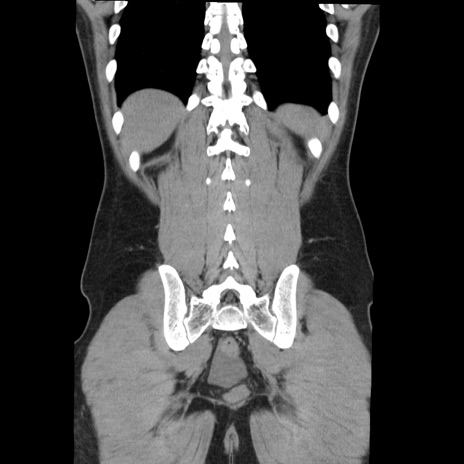

症例36(冠状断像)

【症例】20歳代 男性

【主訴】心窩部痛

【現病歴】今朝より上腹部痛あり。一旦軽快していたが再度出現したため救急要請。昨日夕に白身の魚を含む刺身を食べた。

【身体所見】BP 136/89mmHg、HR 74/min、BT 37.0℃、腹部:膨満、軟、心窩部に圧痛あり。反跳痛なし、筋性防御なし、腸雑音やや亢進あり。

【データ】WBC 17700、CRP 0.48